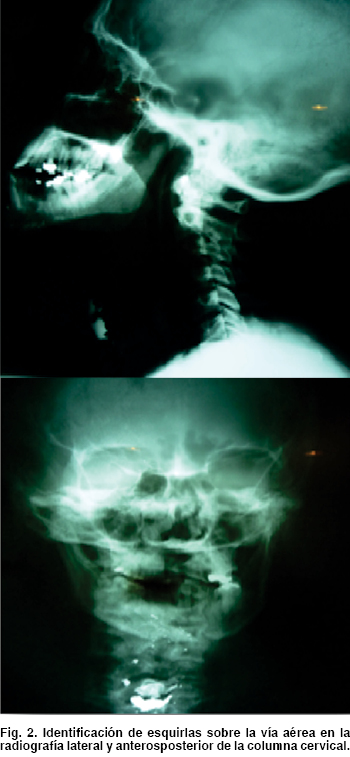

Varón de 46 años de edad, con antecedente de herida penetrante en el cuello con arma de fuego con un orificio de entrada en el maxilar inferior sin orifico de salida, además de compromiso de la vía aérea superior. Es evaluado en el Área de Trauma-Choque, encontrándose, en su evaluación primaria, ansioso, taquipneico con estridor laríngeo, cooperador y con Glasgow de 15 puntos; signos vitales: tensión arterial de 110/60 mmHg, frecuencia cardiaca de 96 latidos por minuto, frecuencia respiratoria de 28 veces por minuto y temperatura de 36 °C, con oximetría de pulso saturando al 90%. Se decidió iniciar tratamiento de acuerdo a las guías internacionales ya establecidas por el protocolo de Apoyo Vital Avanzado en Trauma (ATLS, por sus siglas en inglés), previo apoyo del Servicio de Anestesiología para el tratamiento de la vía aérea difícil (Figura 1). En la evaluación secundaria, se encontraron las siguientes lesiones: herida por proyectil de arma de fuego penetrante a nivel del mentón, fractura expuesta en su parte media con desplazamiento, heridas en el piso de la boca con continuidad hacia el cuello, compromiso de la vía aérea superior y equimosis importante en la cara anterior del cuello. Se solicitaron en el momento, estudio de imagen, y una radiografía lateral y anteroposterior del cuello (Figura 2).